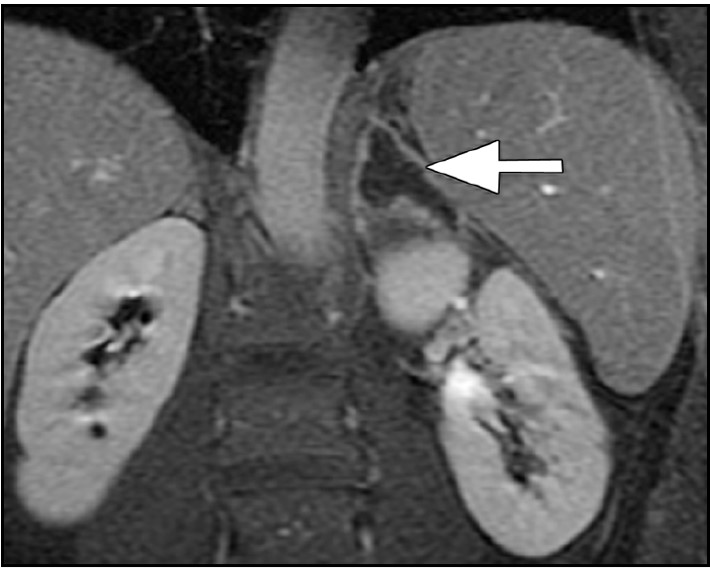

- 【3週間後 MRI 脂肪抑制T1WI】

-

- 右副腎脂肪抑制T1WIで高信号となっており副腎出血を疑う。

- 左副腎の腫大は改善